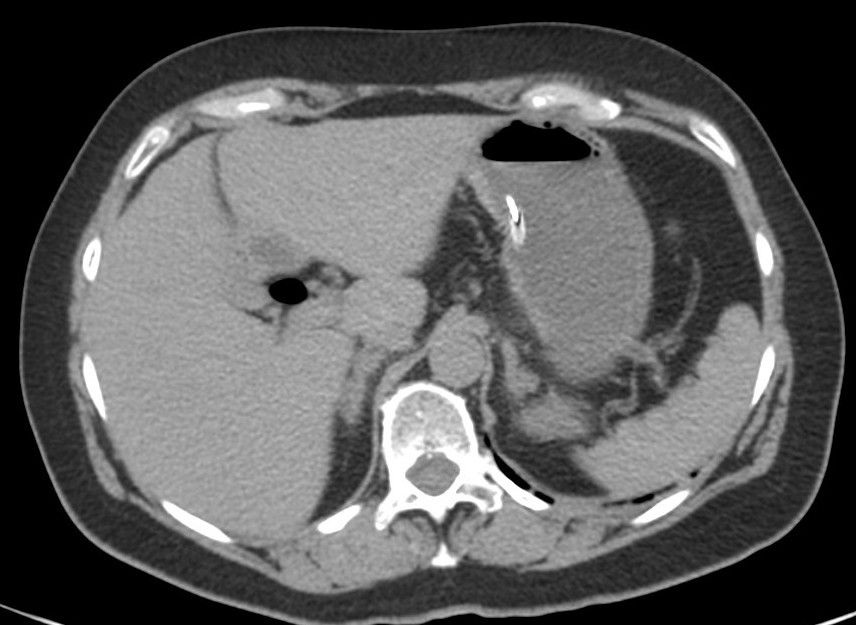

Se realiza un TC abdominal sin contraste:

Observar como posterior a la litiasis hay un cambio de calibre, el segmento que queda de ileon y el colon no están distendidos.

No encontramos ante un Ileo biliar, una obstucción intestinal mecánica ocasionada por una litaisis enclavada en el íleon terminal. La paciente estaba colecistectomizada, por tanto, lo más probable es que haya sido producido por una litiasis residual que pasó desapercibida.